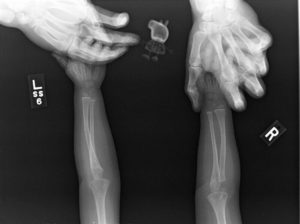

Особенностью рентгеновских лучей является их способность отображать на фотопленке внутреннюю структуру человека, что широко используется во многих отраслях медицины:

- Травматологии. Костная ткань менее прозрачна для электромагнитных лучей, именно поэтому кости отчетливо видны на рентгеновском снимке – это позволяет легко обнаружить любой дефект (трещину, перелом, воспалительный процесс).